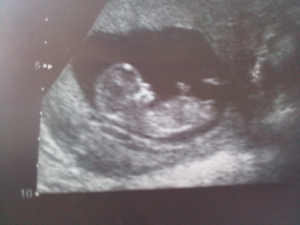

Фотогалерея

Снимок девочки, около 12 недель Снимок двойни Фото на УЗИ, девочка Фото на УЗИ, мальчик Снимок мальчика, 12 недель Разница в снимках УЗИ мальчика и девочки

На 12 неделе при помощи УЗИ уже можно с высокой точностью определить пол будущего ребенка, а также увидеть некоторые его очертания.

Плод уже способен самостоятельно различать движения и сильную вибрацию. При прохождении планового УЗИ можно заметить очертания маленького личика, хоть череп еще не приобрел необходимую форму.

На этом сроке УЗИ показывает не только пол будущего ребенка, но и степень развития половой системы.

Молодые родители уже могут увидеть очертание ручек и ножек, услышать стук сердца.

На УЗИ в этот период можно рассмотреть небольшие ручки и ножки маленького человечка. Если вглядеться в личико ребенка, то на нем уже будут заметны глаза с веками, а также сформированные нос и рот. На руках малыша уже заметны первые ногти.